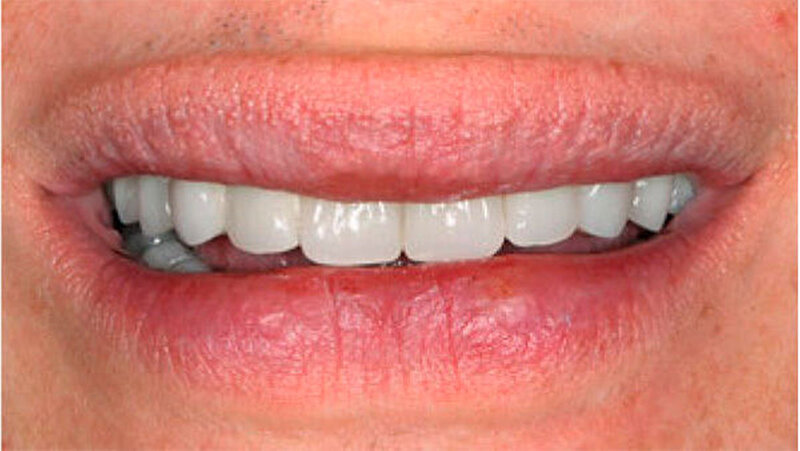

Durch Einbeziehung der Restbezahnung als Pfeilerzähne, und unter Beachtung deren Vitalerhaltung konnte der Patient funktionell und ästhetisch mit stabil verankerten Hybridprothesen rehabilitiert werden (Abb. 14 und 15). Teleskopkronen und -prothesen weisen Studien zufolge eine gute Langzeitprognose auf. Eine regelmäßige Nachsorge ist aber entscheidend für den Erfolg der Rekonstruktion. Da die Speichelmenge bei diesem Patienten im Normbereich liegt, ist diesbezüglich nicht von einem erhöhten Kariesrisiko auszugehen. Eine ungenügende Mundhygiene oder Mitarbeit hingegen stellen Risikofaktoren für biologische Komplikationen wie Parodontitis oder Karies dar. Nachteilig für den Erfolg der Rekonstruktion kann sich die relativ geringe Pfeilerzahl und deren Verteilung im Kiefer auswirken (Wöstmann et al. 2007).

Aufgrund des anatomisch sehr ungünstigen Prothesenlagers war der Erhalt der Restbezahnung im Oberkiefer anzustreben. Nach Kariesexkavation und Wurzelkanalbehandlung konnten beide Zähne mit einer Wurzelstiftkappe versorgt und die alten Prothesen entsprechend umgebaut werden. Im Anschluss an die Meisterabformungen und an die Ausrichtung der Wachswälle wurden die Modelle schädelbezogen einartikuliert, und die Prothesenzähne nach ästhetischen und funktionellen Richtlinien aufgestellt. Eine bilateral balancierte Okklusionsbeziehung konnte umgesetzt werden. Im Oberkiefer wurde eine gerüstverstärkte Totalprothese hergestellt, die auf den beiden Wurzelstiftkappen 16 und 26 verankert war. Im Unterkiefer konnte die Patientin mit einer Totalprothese versorgt werden (Abb. 21 bis 23).

Verbunden mit dem Umstand, dass die Patientin eine ausgeprägte Oligosialie aufweist, ist das Kariesrisiko und hiermit verbunden, auch das Pfeilerzahnrisiko deutlich erhöht. Regelmäßige Kontrolluntersuchungen sind zwingend. Da das Kieferwachstum noch nicht abgeschlossen ist, werden weitere zahnärztliche Behandlungen unumgänglich sein. Diese wenig invasive und relativ zeitnah umsetzbare Therapie erlaubte jedoch eine deutliche Verbesserung der Funktion und der Ästhetik und führte zu einer sichtlichen Stärkung des Selbstbewusstseins. Weitere zukünftige aufwendigere Behandlungsoptionen - insbesondere implantatgetragene Restaurationen - können nun nach abgeschlossenem Wachstum, auf der Basis einer ästhetisch und funktionell akzeptablen Ausgangslage, im Behandlungsteam geplant werden.